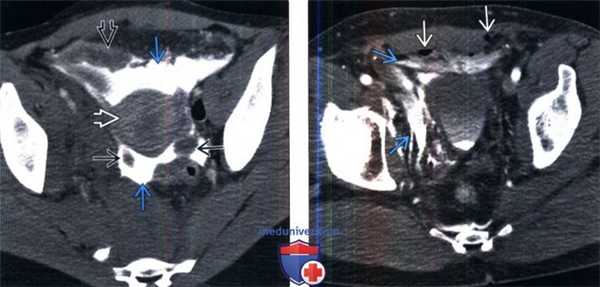

- Простой (4А тип): экстравазация лежит в пределах околопу-зырного пространства

- Сложный (4Б тип): экстравазация распространяется за около-пузырное пространство; бедро, мошонка, половой член, промежность, передняя стенка живота, забрюшинное пространство (околопочечное, околопрямокишечное или собственно забрюшинное пространства) или тазобедренный сустав

- Признак «моляра»: экстравазация мочи в околопузырное пространство принимает округлую конфигурацию краниально и имеет заостренный контур книзу и латерально.